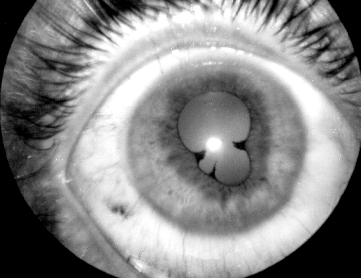

sinechiile iriene posterioare (irido-cristaliniene) reprezinta aderente ale marginii pupilare la cristaloida anterioara, datorita fibrinei si celulelor inflamatorii din umoarea apoasa (Fig. 12.2). Acestea au un aspect dintat (la inceput) si determina deformarea pupilei (vezi plansa), ele putand fi indepartate prin dilatarea pupilei cu instalatii de coliruri midriatice (atropina solutie 1%).

Fig. 12.2 - Sinechii iriene